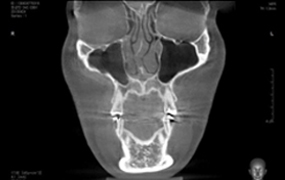

휘어진 정도에 따라 수술방법이 다르기 때문에 3D-CT로 정밀 진단해

근본적인 원인을 찾아내고 1:1 맞춤 상담을 통해 휜 뼈, 휜 연골을 교정합니다.

연골 비대칭 및

비중격 만곡증의 유무

하비갑개 비후 및

코막힘 문제해결

비중격 연골의

상태와 크기 분석

코 뼈의 넓이

비중격만곡증 교정술 및 하비갑개 교정술